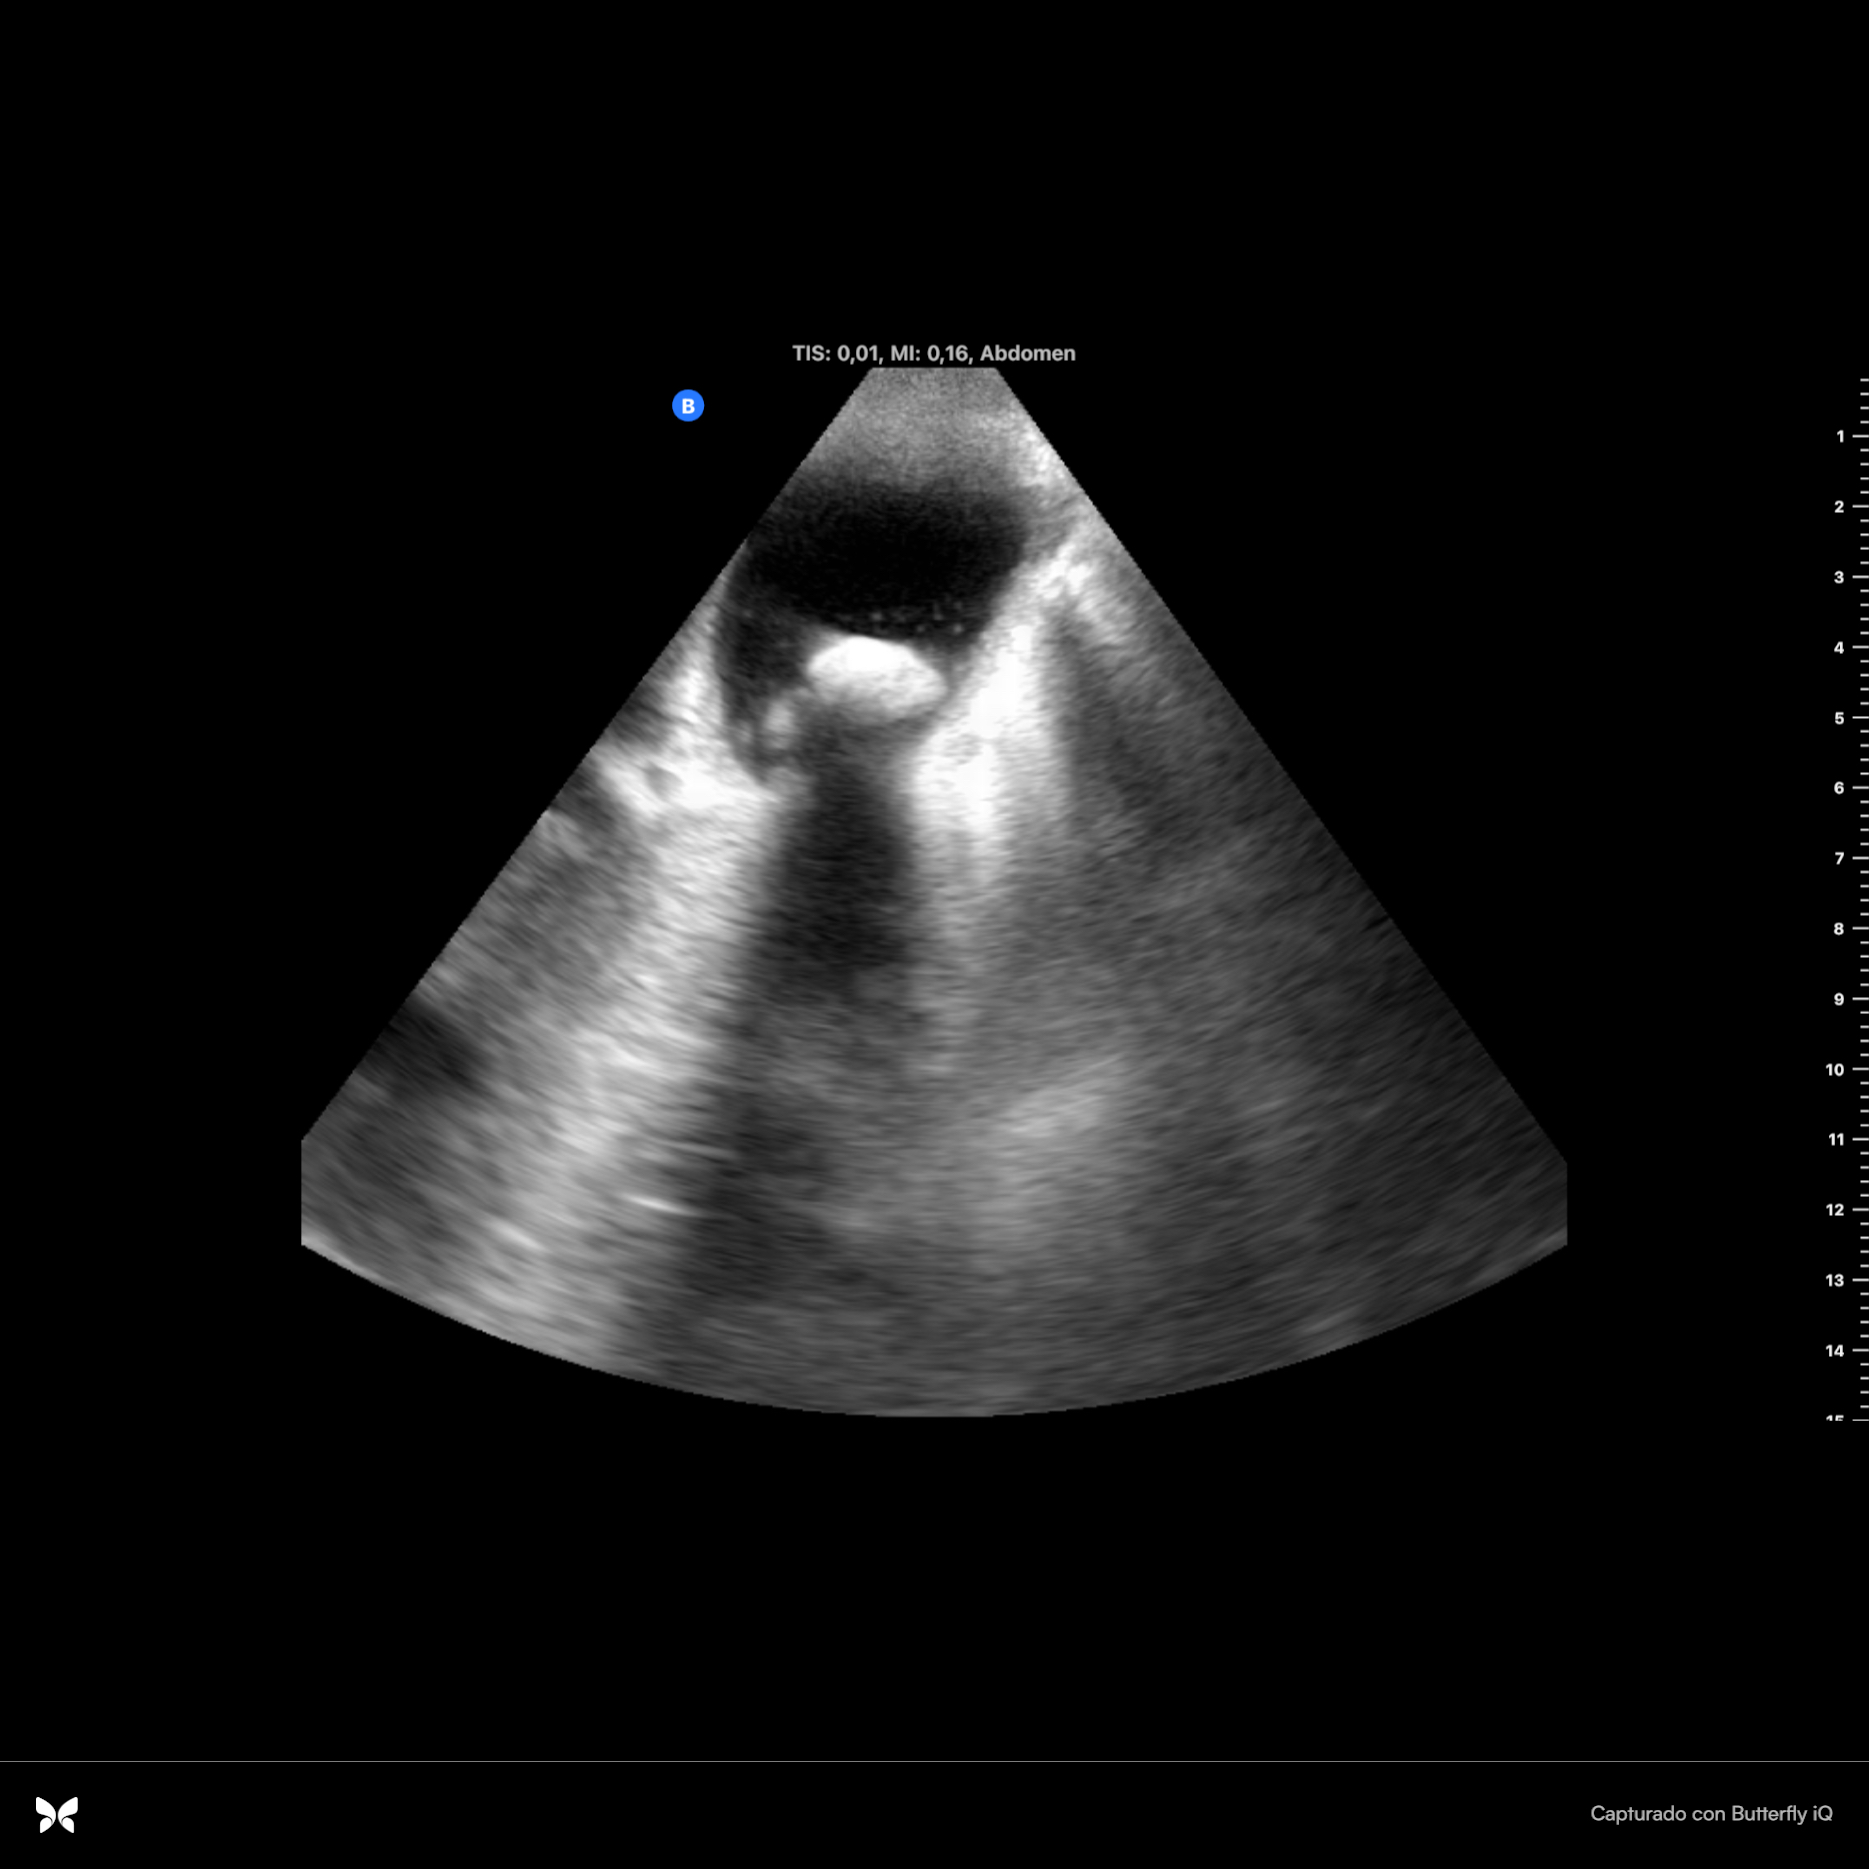

Se observan dos imágenes hiperecoicas en infundíbulo de vesícula que dejan sombra acústica posterior, una de ellas de 2 cm x 0.94 cm con aumento de grosor de vasos suprahepáticas. Parénquima hepático sin alteraciones. Se observa espacio anecoico superior al diafragma. Resto sin hallazgos.